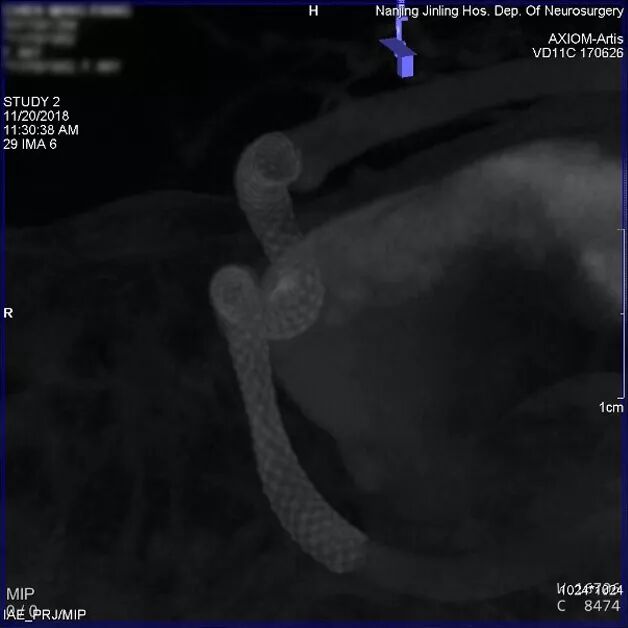

随后术者决定使用球囊锚定微导管技术,从左侧股动脉穿刺置管上球囊,经右侧颈内动脉A1段,通过前交通动脉到达左侧大脑中动脉M1段,同时新的Marksman也超选到左侧大脑中动脉M2段。

球囊经对侧A1和前交通,置于M1

充盈球囊后锚定Marksman微导管,顺利将Pipeline Flex输送通过瘤颈至左侧大脑中动脉M1段。

充盈球囊